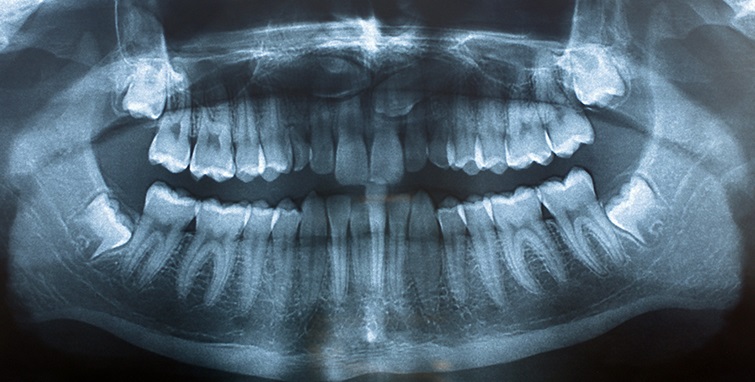

Ортопантомограмма (Панорамный снимок зубов[8]) — рентгеновский снимок, позволяющий провести первичное исследование общего состояния зубов, височно-нижнечелюстных суставов, костной ткани челюстей и гайморовых пазух[6].